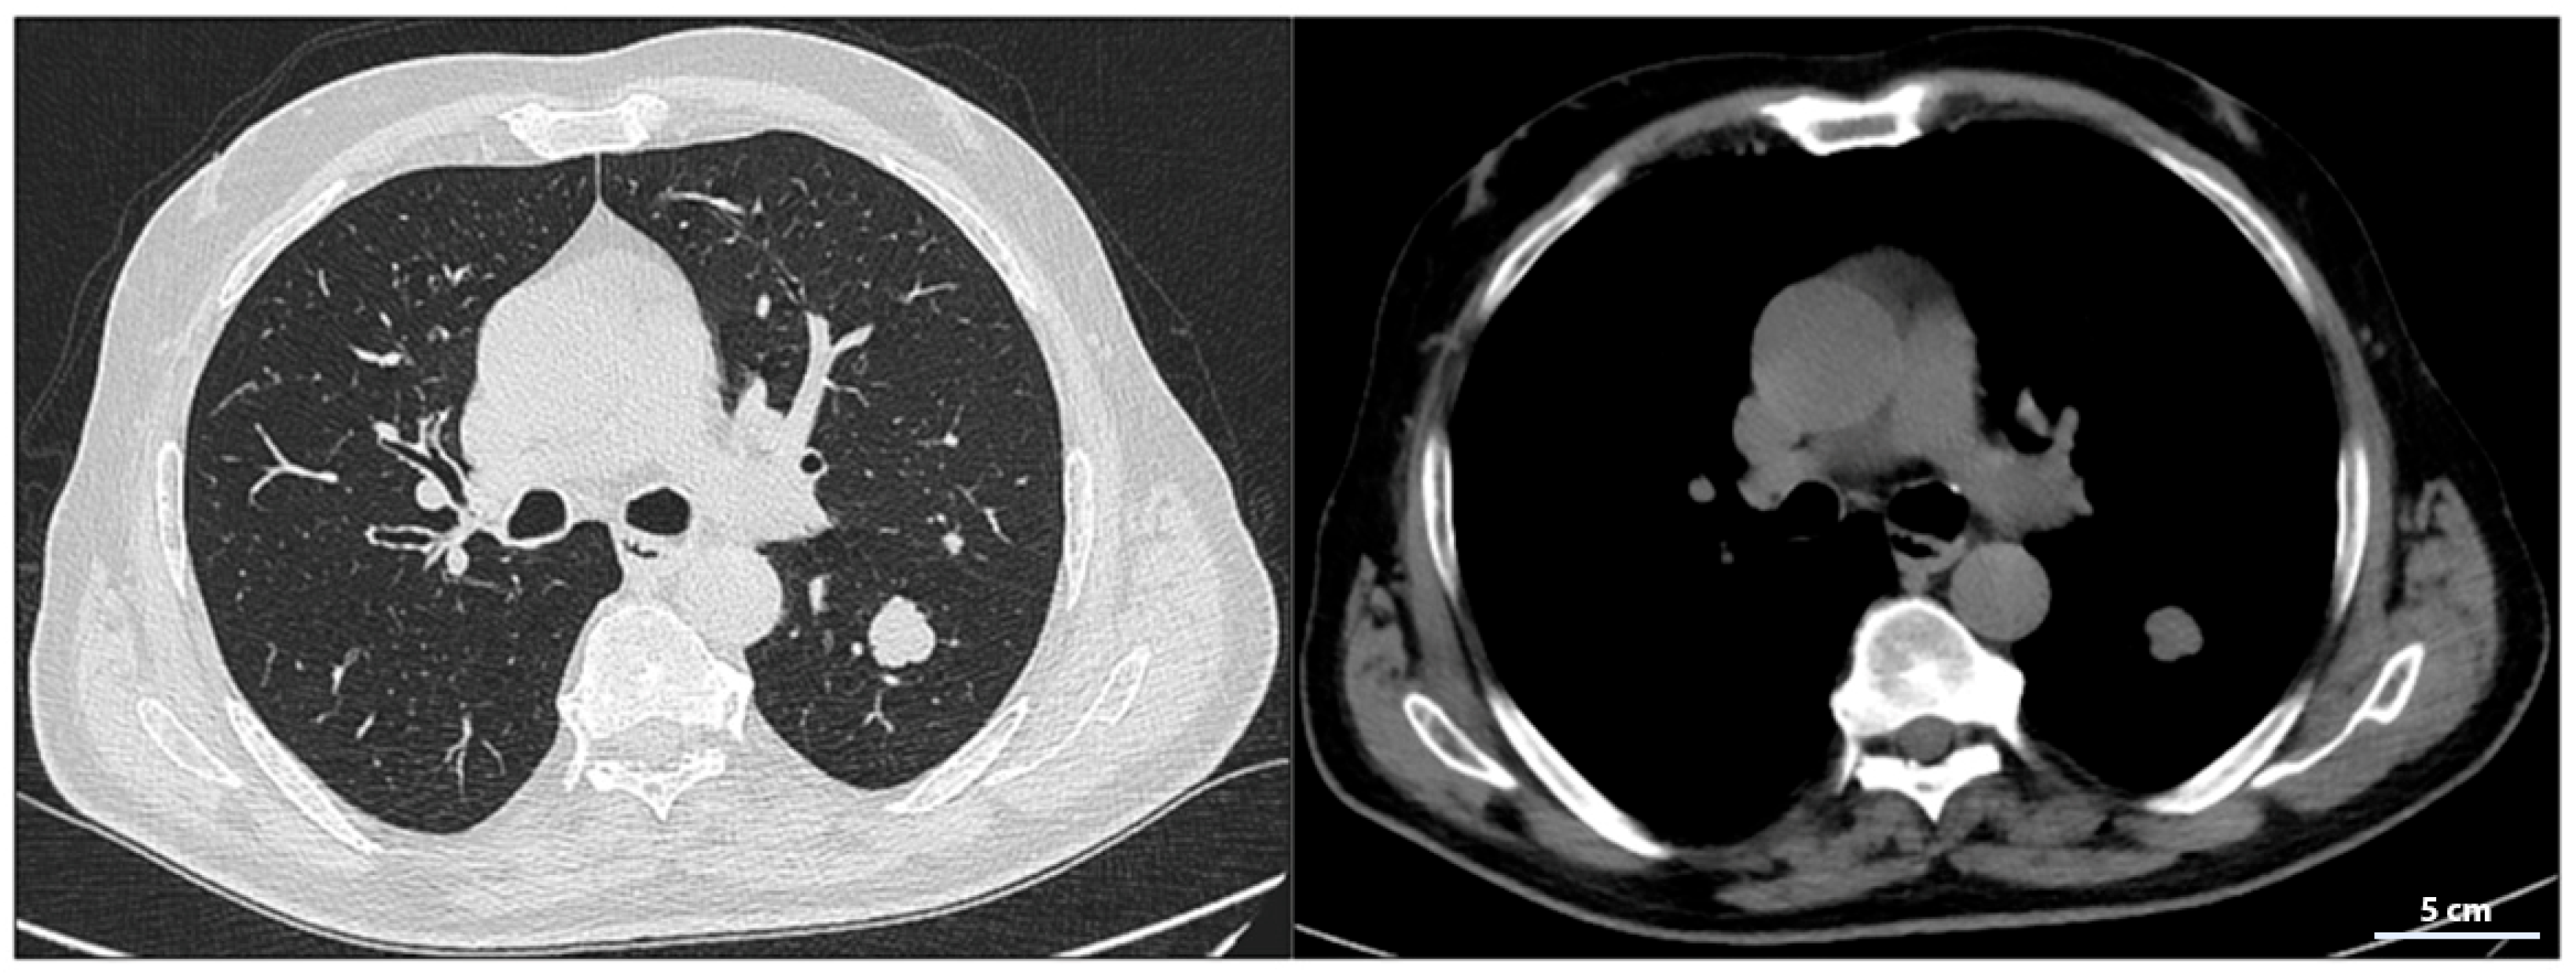

A chest CT scan performed in February 2023 confirmed the presence of a 35 mm solid nodular mass with irregular margins in the apical segment of the lower left lung lobe (Figure 2).

Figure 2.

Chest CT showing a large solid nodular formation in the lower left lung lobe.